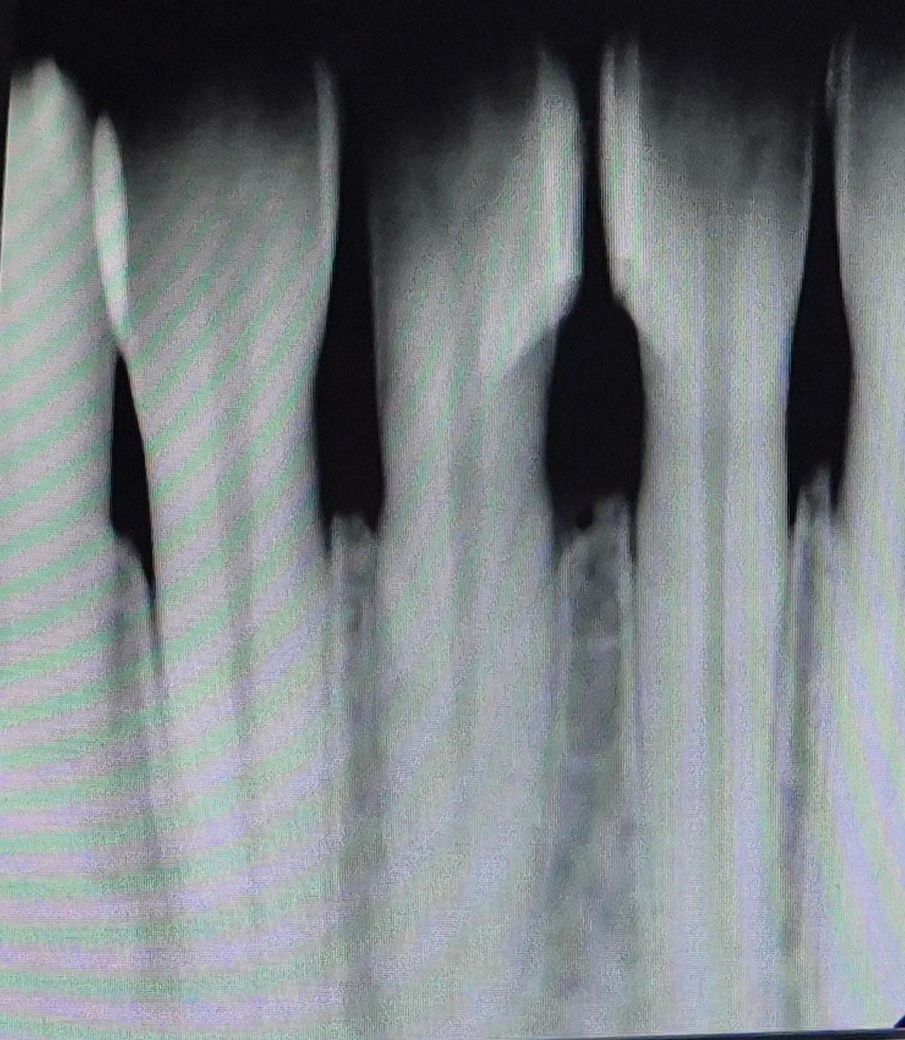

25살 잇몸뼈 상태 심각한가요???

첫번째 치과에서는 잇몸뼈만 조금 내려갔다고 하고 염증이나 충치도 아예 없고 아래앞니쪽 치석이 있는 편이니 스케일링만 받으면 된다고 했어요.

질문 1번. 25살 치고 잇몸뼈 상태가 많이 안 좋은 편인가요? 신경치료할까봐 너무 두렵습니다.

• 2번 째 사진

25살 치고 잇몸뼈 상태가 안 좋은 편은 맞으며 불편한 느낌이 계속 드는 경우 가보시는 게 좋습니다.

다른 치아들의 잇몸뼈는 괜찮은데 앞니의 경우는 잇몸뼈가 나이에 비해서 많이 내려간거 같습니다. 정기적으로 치과를 다니면서 관리를 받으시는게 좋을것같습니다.